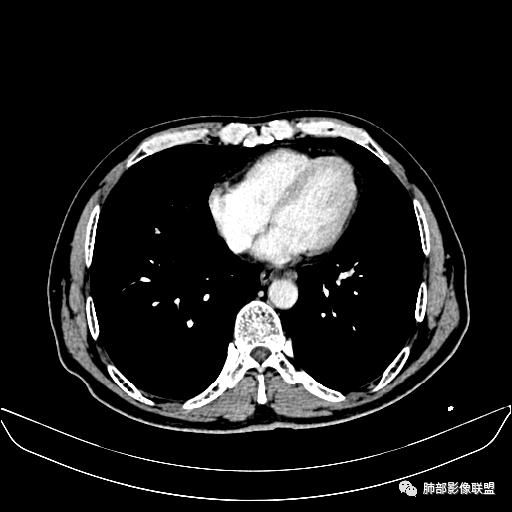

入院CT

老年男性,因“咳嗽咳痰1月余。”入院。病程中咳嗽咳痰,咳黄白痰,间断咯少许鲜红色痰血。PPD阳性。胸CT:右肺中叶外侧段支气管管腔阻塞,大片实性病变,病灶边缘光滑,部分边缘膨隆,可见分叶,肺门及纵隔可见肿大淋巴结,并可见钙化。增强可见病灶明显强化,而且延迟强化明显,病灶内多发低密度区,内见血管影,血管变细、部分血管破坏。考虑恶性病变可能性大,鉴别慢性肉芽肿性病变。

右肺中叶外侧段管腔阻塞、实性病变,病灶边缘光滑,可见分叶,肺门及纵隔可见肿大淋巴结,并可见钙化。增强可见病灶内多发低密度区。

老年男性,咳嗽、咳痰1月余,间断血痰。PPD阳性。

胸CT:跨叶大肿块,主体在中叶,右中叶外侧段支气管阻塞,病灶部分边缘膨隆,可见分叶,部分边缘平直,肺门及纵隔可见肿大淋巴结。增强病灶不均匀强化,延迟强化明显,病灶内多发低密度区,内见血管飘浮,部分血管变细、模糊。考虑:恶性病变可能性大,大细胞?淋巴瘤?鉴别慢性肉芽肿性病变。